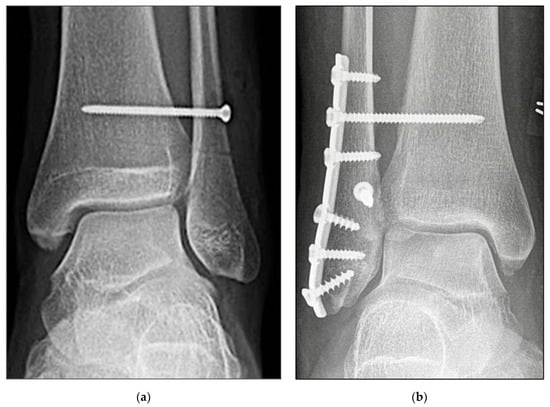

2.3. Surgical Procedure